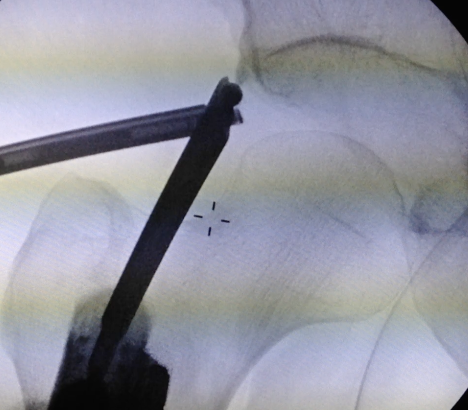

Mid anterior portal